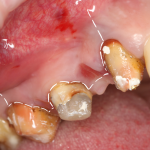

Необходимым условием для проведения этого вмешательства является стадия ремиссии воспалительного процесса в области удаляемого зуба, отсутствие или небольшие размеры очагов хронического воспаления в прикорневой зоне (рис 49, 50, 51):

Рисунок 49, 50, 51. Проведение операции синуслифтинга одномоментно с удалением зуба: слева – скелетирование стенки верхней челюсти, подготовка к удалению зуба, в центре – лунка удаленного зуба (виден небольшой очаг деструкции костной ткани вследствие хронического периодонтита), справа – заполнение субантральной полости спейсером.

К установке имплантов можно приступать через 3-4 месяца (рис 52, 53):